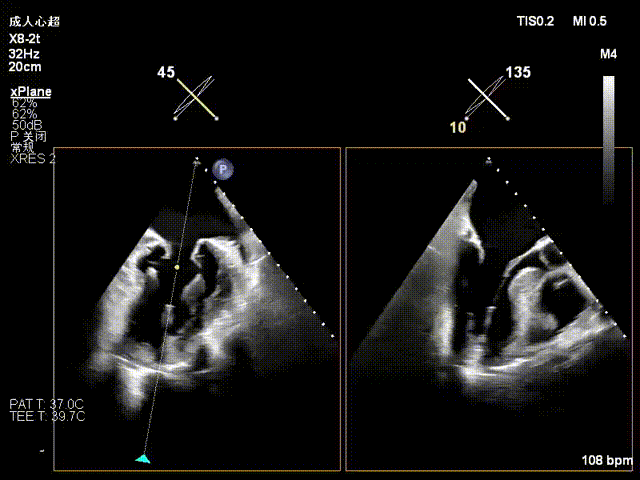

患者全麻后仰卧位,常规消毒铺巾,置入下食道超声探头。于左前胸第五肋间做小切口,暴露心尖,全身肝素化后,心尖穿刺,逐步送入二尖瓣夹系统。术中在超声引导下,分别于C1及A1/P1区植入2枚ValveClamp®二型(MVC-Ⅱf)二尖瓣夹,夹合后超声显示二尖瓣反流明显减轻,随即释放夹子。术后置左侧胸腔引流管1根,逐层关闭胸壁,患者顺利转入ICU观察。

一夹后图像,残余反流位于2区

确认夹子位于反流区

术后即刻反流降为少量,剩余瓣口面积2.57cm²,平均跨瓣压差2mmHg。

术后复查超声心动图显示:二尖瓣轻度返流,三尖瓣中度返流,二尖瓣可见金属夹回声,启闭正常;各心室大小正常,升主动脉不宽,主瓣回声增强,启闭良好;二尖瓣舒张期峰值流速1.4 m/s,功能面积2.1 cm²,跨瓣平均压差约4 mmHg。